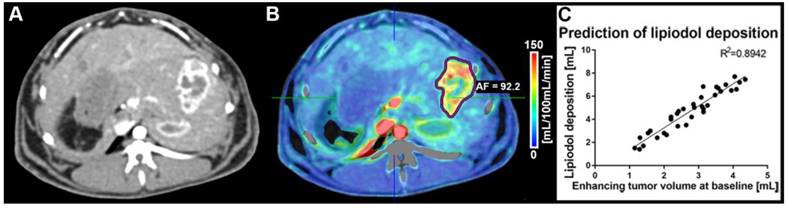

CT volumetric measurements were obtained on native and CECT volumetric scans acquired at baseline and before each pre-planned sacrifice time point. Baseline imaging was used to quantify the enhancing tumor volume prior to cTACE to be used for comparison with Lipiodol deposition volumes. At baseline, the mean total tumor volume was 15.1 cm3 and measured 14.4 cm3, 11.5 cm3 and 15.7 cm3 at 24 h, 7 days and 20 days, respectively. The enhancing tumor volume was measured using CECT images and expressed as an absolute volume in cm3/mL. Lipiodol deposition was measured on native CT images using qEASL as already described. Figure 1 depicts the relationship between enhancing tumor volume at baseline and Lipiodol deposition as measured 24h post cTACE. Persistent retention of Lipiodol in the tumor across all time points was measured (Figure 2). Lipiodol deposition was mainly visible in the rim of the tumor and was mostly absent in the tumor core. This observation correlated well with the vascularization/enhancement pattern of rim hyper-enhancement. A strong correlation (R2 = 0.894) was found between the volume of enhancing tumor tissue at baseline and the tumor volume filled with Lipiodol post TACE (R2=0.894) (Figure 1).

Figure 1

(A) Contrast-enhanced dynamic perfusion CT scan at baseline (arterial phase, 20 s delay, before TACE) showing the tumor implanted in a left lobe of the liver. The tumor rim is enhancing, while the tumor core is not taking up contrast. (B) Arterial flow (AF) color map superimposed on the contrast-enhanced CT scan shown in (A). The tumor was segmented (purple outline) and an average AF of 92.2 mL/100 mL/min was calculated for the lesion. (C) Correlation between enhancing tumor volume (calculated using the qEASL technique on perfusion imaging data) and lipiodol deposition post-cTACE (all timepoints) as calculated with qEASL using the native CT images (R2=0.8942).